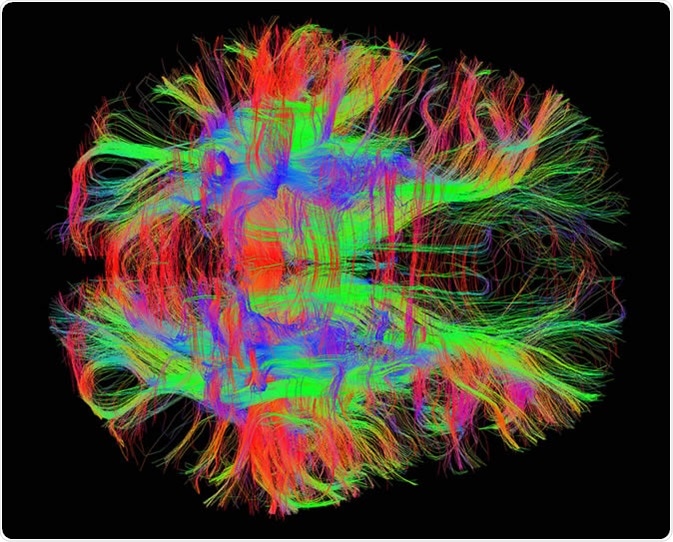

Diffusion tensor imaging (DTI) tractograpy. The color-coding of

Diffusion Tensor Imaging (DTI) revealing connectivity in the brain

Using Diffusion Tensor Imaging (DTI), axonal fiber tractography

A) Diffusion tensor imaging (DTI)-based whole-brain tractogram in